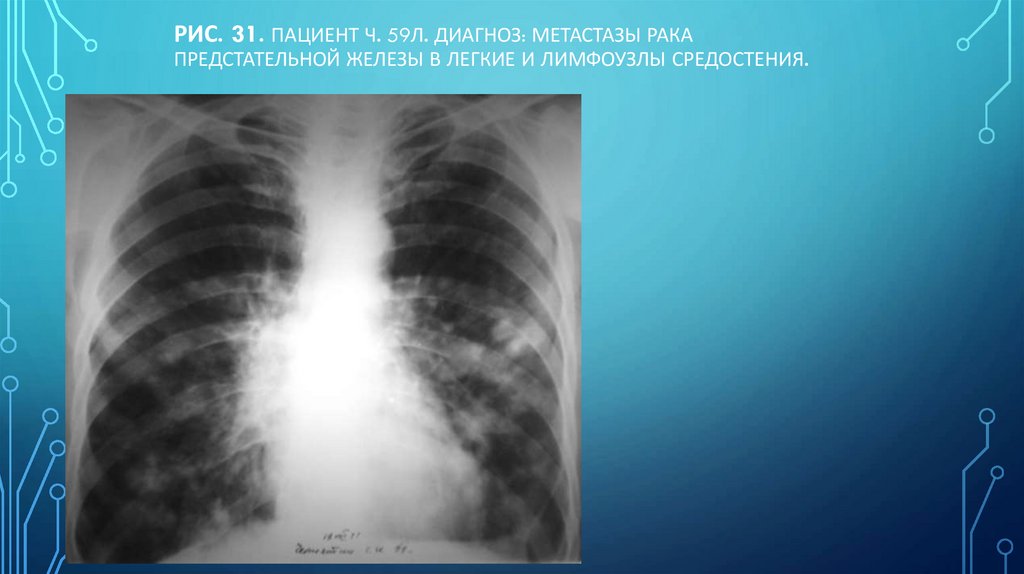

Рис. 31. Пациент Ч. 59л. Диагноз: Метастазы рака предстательной железы в легкие и лимфоузлы средостения.

112. Рис. 31. Пациент Ч. 59л. Диагноз: Метастазы рака предстательной железы в легкие и лимфоузлы средостения.

РИС. 31. ПАЦИЕНТ Ч. 59Л. ДИАГНОЗ: МЕТАСТАЗЫ РАКА

ПРЕДСТАТЕЛЬНОЙ ЖЕЛЕЗЫ В ЛЕГКИЕ И ЛИМФОУЗЛЫ СРЕДОСТЕНИЯ.

Н.С. ВОРОТЫНЦЕВА. С.С. ГОЛЬЕВ РЕНТГЕНОПУЛЬМОНОЛОГИЯ